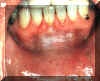

Esta lesión en el piso de la boca

y en el reborde alveolar es bastante sospechosa. La presencia de

queratosis con una zona central de ulceración hace pensar en la

posibilidad de un cáncer. Si la lesión de este tipo no desaparece en

un período corto después de iniciada una terapia consevadora, debe

realizar la biopsia en forma inmediata. |